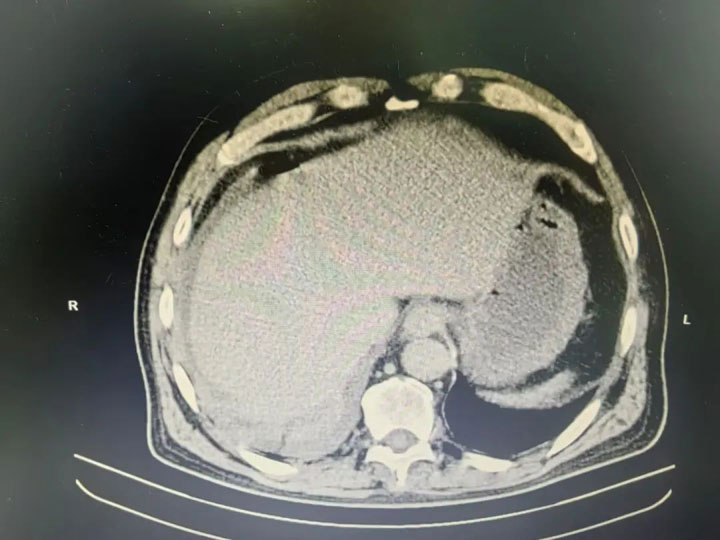

五一劳动节期间,60多岁的林师傅因“上腹部疼痛伴加重3天”就诊广济医院普外科,医生查体后为其行影像检查,CT提示:消化道穿孔。

无影灯亮起,手术室内,外科代坤主任、缪继斌主任为患者仔细探查,见其肠间隙大量脓液包裹、腹腔大量脓苔,胃窦前壁见直径约1.5cm穿孔,术中诊断“感染性休克、弥漫性腹膜炎、胃窦前壁穿孔”。麻醉科卜美林主任紧盯监护仪,“危重患者更要严密监测,影像提示肺部感染,患者术中血氧饱和数值较低,需要格外留心。”